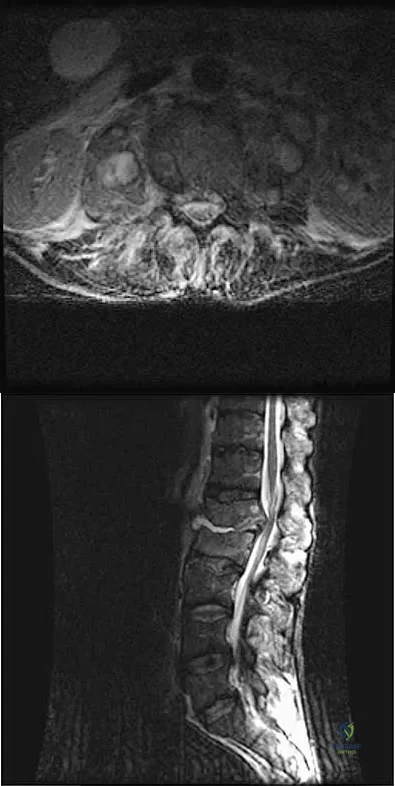

Question 16

Figures 3a and 3b show the MRI scans of a patient with neck pain. What is the most likely diagnosis?

Explanation

Question 43High Yield

A 60-year-old woman with a history of breast cancer has progressive paraparesis. The MRI scan is shown in Figure 28. What form of management is most likely to restore or maintain ambulation?

Explanation

Question 56

A 32-year-old man notes increasing back pain and progressive paraparesis over the past few weeks. He is febrile, and laboratory studies show a WBC of 12,500/mm3. MRI scans are shown in Figures 6a and 6b. Management should consist of

Explanation

Question 80High Yield

Figure 10 shows the MRI scan of a 56-year-old woman with metastatic breast cancer who now reports progressive paraparesis. Her general health remains good. Treatment should consist of

Explanation